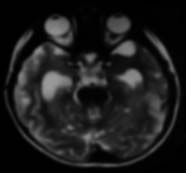

Case 02

braintumor02.jpg

4-yo, girl tilting the head to the right

HE brain stem glioma, giant multinuclear cell+, MIB-1 50%, IDH1 R132H negative, p53++

予後はいくらもかわらない。いまのintegrated diagnosisにあわせるとやっかい。

大事なのはhistonの異常をしらべなければならない. Histon H3.1 HIST1H3BK27M

この遺伝子異常によるタンパク質は免疫染色で検出できる抗体がある。かならずしもsequenceしなくてよい.

Final integrated diagnosis

Integrated diagnosis: Diffuse midline glioma(brainstem glioma) H3K27M-mutant, WHO gradeIV

Histological diagnosis: Glioblastoma

Histological grade: Grade IV

Molecular information: